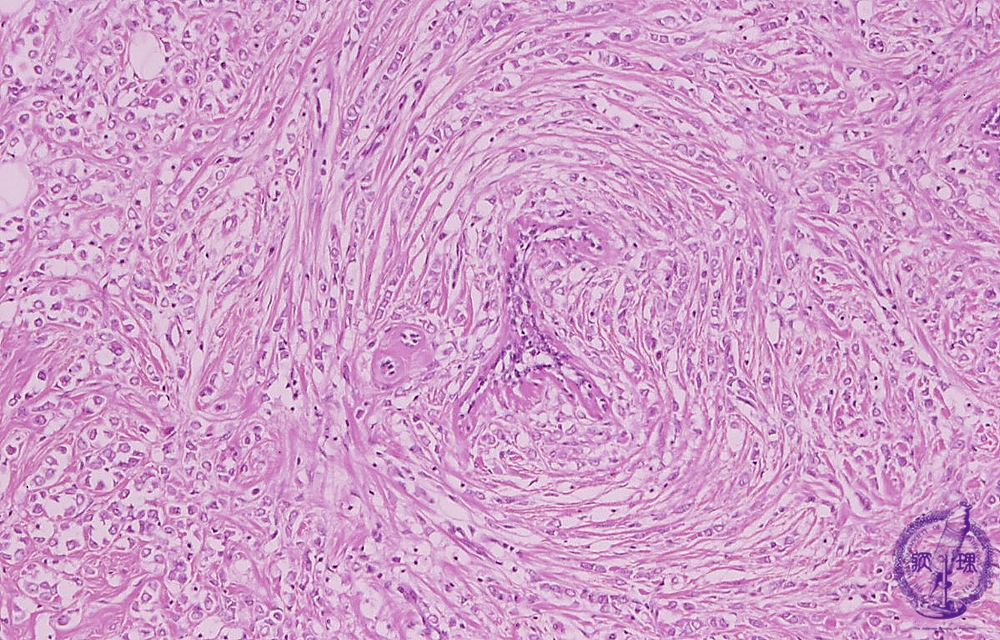

Microscopic image(HE stain, high power view):Stromal invasion of lobular carcinoma. Relatively small carcinoma cells with high N/C ratio infiltrated to the stromain a so-called “Indian-file”manner(inset, arrow).This finding is characteristic of invasive lobular carcinoma.